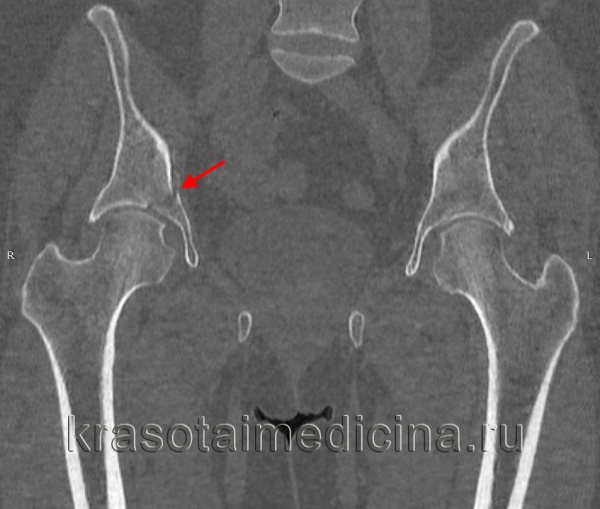

Межвертельные переломы являются внекапсульными и проходят через губчатую кость между большим и малым вертелами. Они обычно встречаются у пожилых больных в возрасте от 66 до 76 лет, у женщин в 4—6 раз чаще, чем у мужчин. Кровоснабжение этой области очень хорошее благодаря тесному прилеганию окружающей мускулатуры и наличию губчатой кости.

Внутренние ротаторы бедра остаются прикрепленными к проксимальному фрагменту, в то время как короткие наружные ротаторы остаются прикрепленными дистальнее головки. Классификацией Boyd и Griffin пользуются большинство ортопедов, однако врачам неотложной помощи достаточно классифицировать эти переломы только на стабильные (I тип) и нестабильные (II тип).

Класс В, I тип: стабильные межвертельные переломы. Единичная линия перелома пересекает кортикальный слой между двумя вертелами. Между диафизом и шейкой бедренной кости смещения нет. Класс В, II тип: нестабильные межвертельные переломы. Между диафизом и шейкой бедра имеется несколько линий перелома или фрагментация с сопутствующим смещением.

Большинство этих переломов является следствием прямой травмы, например при падении на большой вертел или при передаче силы по оси бедренной кости. При воздействии большей силы это повреждение может сочетаться с переломами большого или малого вертела. Мышцы, прикрепляющиеся к вертелам, способствуют дальнейшему смещению фрагментов.

У больного отмечаются болезненность, припухлость и кровоизлияния в области тазобедренного сустава. Обычно наблюдается укорочение конечности с наружной ротацией вследствие тяги подвздошно-поясничной мышцы.

Для выявления этих переломов обычно достаточно снимков в прямой и боковой проекциях.

Лечение межвертельных переломов бедра

Неотложная помощь при этих переломах включает иммобилизацию больного, анальгетики и госпитализацию. Повреждения II типа лучше всего лечить методом открытой репозиции с внутренней фиксацией, позволяющей раннее начало движений. Переломы I типа можно лечить постельным режимом, скелетным вытяжением по Russell с последующим переходом от частичной к полной нагрузке на конечность.